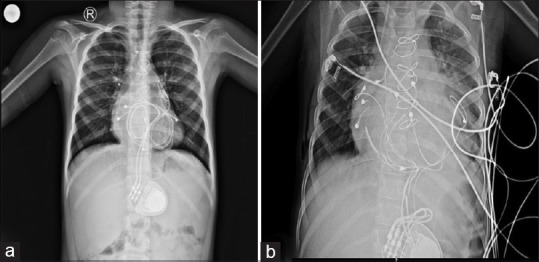

Cardiac strangulation is a rare phenomenon in children following epicardial pacemaker implantation, caused by compression of the heart and great vessels by the epicardial pacemaker wires. We report a rare case of cardiac strangulation presenting after 8 years of epicardial pacemaker implantation. On routine follow-up, computed tomography angiography showed significant extrinsic compression of the mid-left anterior descending (LAD) artery by the epicardial pacing wire. She was referred to our department for myocardial perfusion imaging (MPI), which showed significant inducible ischemia in the LAD territory. Following this, she underwent a successful pacemaker reimplantation. MPI can, thus, act as a good tool to assess the functional significance of the compression caused by strangulation of the heart by pacemaker leads in asymptomatic patients.